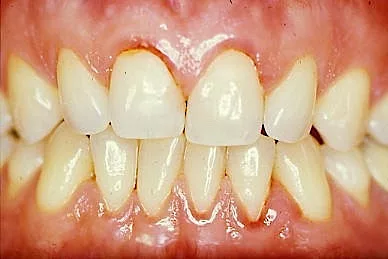

Le saignement, le changement de couleur ou de texture des gencives constituent les premiers signes de de la maladie parodontale.

D’autres symptômes comme la mobilité des dents, la rétraction des gencives ou une mauvaise haleine doivent alerter sur une altération de la santé parodontale.